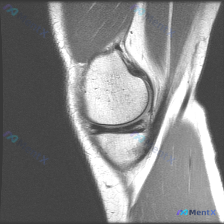

今天看到一份很有代表性的读片病例,整理出来和大家分享一下,核心问题就是:临床怀疑半月板异常,但是只给了一张膝关节矢状位T1加权MRI,阅片没发现明确异常,这个情况该怎么分析?

这是单张膝关节正中矢状位T1加权像,图像质量清晰,没有运动伪影,能看到股骨远端、胫骨近端、髌骨、髌下脂肪垫这些结构,我们来逐层看:

- 骨质结构:股骨和胫骨骨髓脂肪信号均匀,没有异常低信号灶,骨皮质连续光滑,没有骨质破坏,软骨下骨板形态正常,也没有明显骨赘,髌骨形态和髌股关节间隙都正常

- 半月板:这个层面的半月板前后角都是均匀低信号三角形,形态规整,没有内部信号异常增高,也没有看到延伸到关节面的撕裂高信号

- 韧带:前交叉韧带走行正常,条索状低信号,纤维连续;后交叉韧带因为切面限制没完全显示,但看到的部分连续性良好

- 软组织:髌腱信号正常,髌下脂肪垫没有水肿,关节腔没有明显异常积液,周围软组织层次清晰